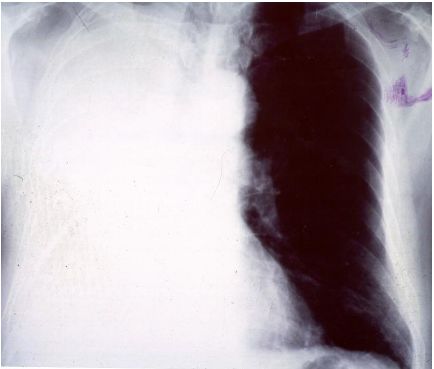

13. 39歲男性有多重性伴侶,因持續發燒及體重減輕3公斤,而且逐漸感到呼吸困難而入院,身體檢查發現口腔有白色珠菌 (Candida)感染,胸腔 X光如圖35 ,血液檢查結果: HIV Test :陽性、血液淋巴球比率: 8%、 CD3:34% 、CD4:0.2%、 CD8:36% 、CD19:4%,肺部灌洗液檢出囊胞蟲(Pneumocystis carinii),下列敘述何者為真?a. 囊胞蟲肺炎 ( Pneumocystis carinii pneumonia ) 典型表現為兩側肺門旁之浸潤,很快迅速進展成瀰漫性兩側肺部浸潤b. AIDS合併囊胞蟲肺炎患者的死亡率為單獨感染囊孢蟲肺炎者之三倍c. 所有囊胞蟲肺炎患者均需住院治療d. 大部HIV合併囊胞蟲肺炎病患的症狀均為突發性咳嗽,高燒而無呼吸困難症症狀e. Trimethoprium-Sulfamethoxazole仍為治療及預防囊蟲肺炎之首選藥物